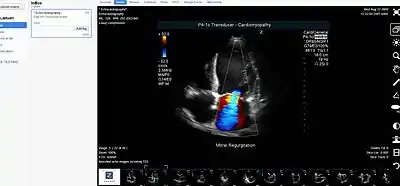

An image displayed on a medical image sharing platform

Medical image sharing is the electronic exchange of medical images between hospitals, physicians and patients. Rather than using traditional media, such as a CD or DVD, and either shipping it out or having patients carry it with them, technology now allows for the sharing of these images using the cloud. The primary format for images is DICOM (Digital Imaging and Communications in Medicine). Typically, non-image data such as reports may be attached in standard formats like PDF (Portable Document Format) during the sending process. Additionally, there are standards in the industry, such as IHE Cross Enterprise Document Sharing for Imaging (XDS-I), for managing the sharing of documents between healthcare enterprises. A typical architecture involved in setup is a locally installed server, which sits behind the firewall, allowing secure transmissions with outside facilities. In 2009, the Radiological Society of North America launched the "Image Share" project, with the goal of giving patients control of their imaging histories (reports and images) by allowing them to manage these records as they would online banking or shopping.[1]